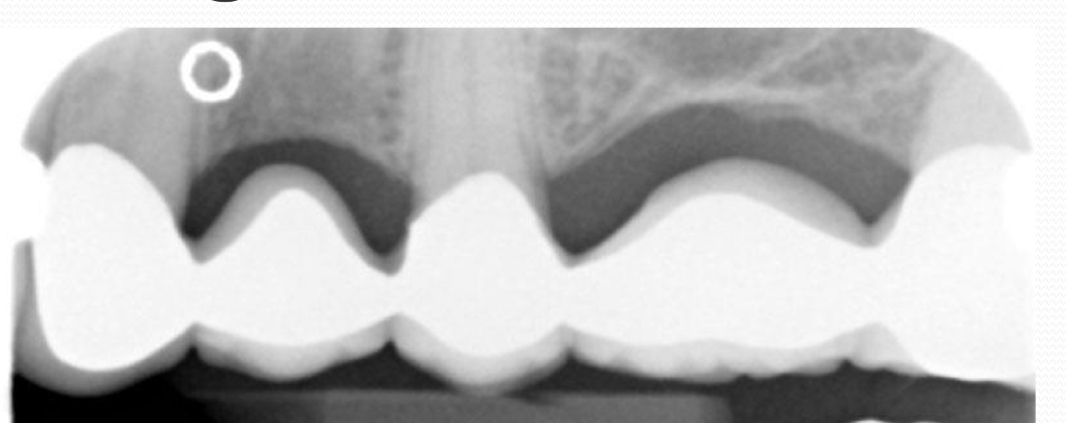

Amalgam restorations

Amalgam fragments